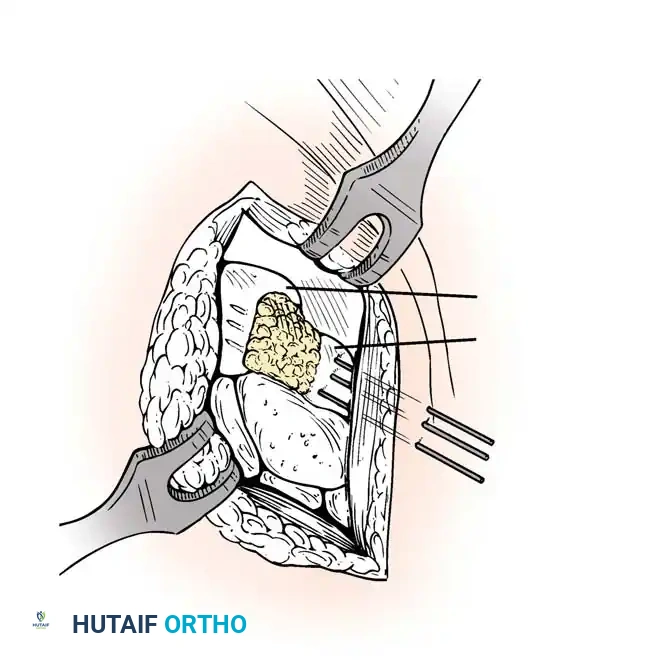

- Bone Grafting: A local distal radial bone graft portal is utilized. Cancellous bone is harvested from the distal radius metaphysis to augment the fusion sites.

- Plate Application: A 3.5-mm dynamic compression plate (DCP) is applied from distal to proximal. The plate is specifically contoured to provide 10 to 15 degrees of wrist extension. The plate spans the local radial bone graft augmentation, ensuring rigid compression across the fusion mass.